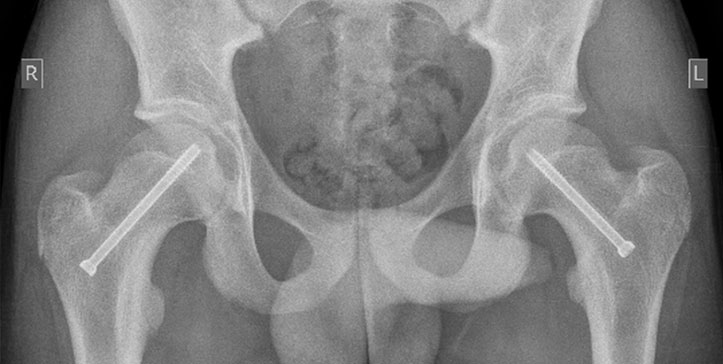

This adolescent had both hips pinned. There is discrepancy of opinion between surgeons whether both sides should be pinned initially, or whether to only operate on the second hip if symptomatic. Advances that have been made are using a different entry point to ensure the screw is aimed for the centre of the head, the operation might be done through a 1cm incision, and where possible stainless screws are easier to subsequently remove. The screw need not be removed as a rule.